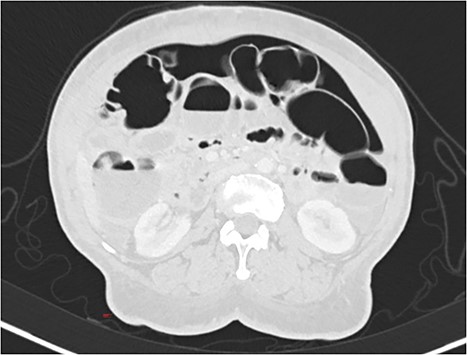

A 63-year-old woman underwent an elective hysterectomy and bilateral adnexectomy due to a large right adnexal mass (290 × 190 mm). On the sixth postoperative day, she developed nausea and vomiting, along with abdominal distension and generalized abdominal pain, without peritoneal signs or guarding. An abdominal X-ray was requested, which showed pneumoperitoneum and multiple air-fluid levels in the small intestine. Blood tests were unremarkable. An abdominal and pelvic computed tomography (CT) scan was also performed, revealing “pneumoperitoneum in a quantity above what would be expected given the postoperative timeline, with no image suggestive of hollow viscus or vaginal cuff dehiscence.” (Figs 1 and 2). Based on the clinical findings, a conservative approach was chosen. A nasogastric tube was placed, and the patient was put on a nil-by-mouth diet. Two days later, she began an oral diet and resumed intestinal transit, maintaining a favorable clinical course for the remainder of her hospital stay.